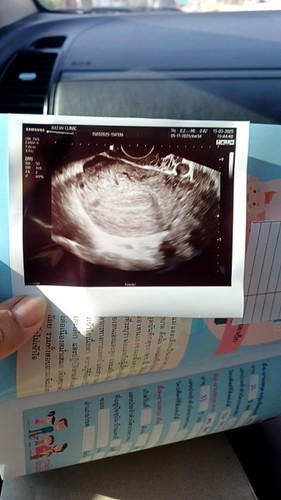

วันนี้ไปซาวดูไม่เจอถุงตั้งครรภ์ แม่ๆ เจอถุงตั้งครรภ์กี่week คะ ตอนนี้อายุครรภ์ได้ 6 week

เค้าเจอตอน5วีคค่ะ แต่ยังไม่เห็นน้องเพราะน้องตัวน้อยค่ะ บางคนก็อาจจะเจอถุงตอนอายุครรภ์มากกว่านี้ค่ะ อย่ากังวลไปเลยนะคะ

ใจเย็นๆนะคะแม่บางทีน้องอาจจะยังเล็กอยู่ก็ได้ค่ะเราเจอตอน 6 วีค + 1 วันค่ะ

ของเราเจอตอนไปซาวครั้งแรก 6 วีค 5 วัน เห็นหัวใจน้องแล้วด้วย

6วีคค่ะ ซาวด์ทางช่องคลอด เห็นตัวน้องกับหัวใจเต้นคะ